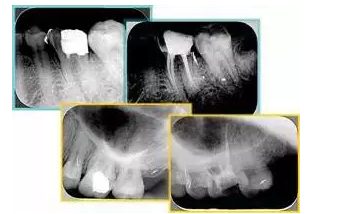

6. 術(shù)后 X 線片

術(shù)后 X 線片用來評定根管充填 長度、致密度(管壁清晰、側(cè)枝)等指標(biāo)。

左圖為根管充填術(shù)后 X 線片。圖中可見,根管充填較好。右下圖有白色小點(diǎn),為側(cè)方加壓導(dǎo)致糊劑擠出所致,表明根管充填比較致密。

致密、恰到好處的充填可去除干凈根管里感染灶,機(jī)體逐漸恢復(fù)。

多根牙時候需進(jìn)行偏移投照,正位投照無法說明具體哪根牙根管充填效果。 二、根管預(yù)備及充填要求